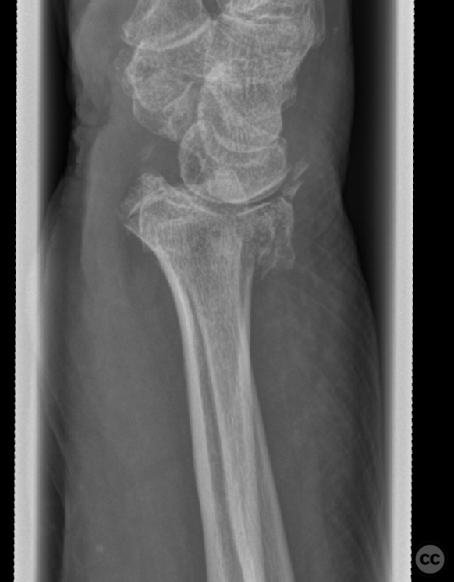

Clinical and radiological findings:  A 72-year-old female sustained a multifragmentary, dorsally displaced distal radius fracture after a fall down stairs. Initial reduction revealed a 180-degree flipped fragment of the volar ulnar articular margin, unreducible by closed means. There was no mention of associated neurovascular compromise or open injury. Radiographs and intraoperative fluoroscopy confirmed the presence of a multifragmentary intra-articular fracture (AO/OTA 23-C3), with a flipped volar ulnar fragment and radial styloid impaction. The distal radioulnar joint alignment was restored postoperatively.